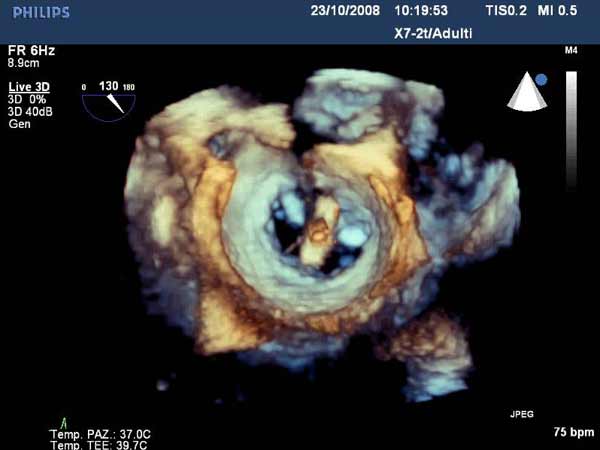

Figure 4

In absence of controlled clinical trial data which are forthcoming from the EVEREST II randomized study, the indications for the MitraClip therapy are currently based on registry experience and will evolve as the technique improves, experience is growing and the data to demonstrate efficacy and safety becomes available. At this time, the best indication for the MitraClip therapy is for symptomatic patients with clinically significant functional or degenerative MR who are at high or increased risk for open heart surgery. From a pure technical standpoint, the procedure so far has only been demonstrated in a subgroup of patients with specific anatomical characteristics which are summarized below and shown in Figure 3. Anatomic suitability is assessed by transesophageal echocardiography, and mitral regurgitation should originate from the central portion of the valve involving the A2-P2 segments, since the device is not ideal to work in the commissures at this time; the mechanism of MR can be either a prolapse/flail or MR due to restricted leaflet motion unrelated to rheumatic disease; the separation between the two leaflets at the site of regurgitation should be limited; severe annular dilatation and/or severe calcification should be absent or is relevant. In case of flail, the flail segment width should be less than 15 mm, and the flail gap less than 10 mm. Figure 4 is a 3D echo image of a patient with posterior leaflet prolapse selected for MitraClip therapy. In case of functional MR, the leaflets should have a minimal residual tissue available for coaptation with the MitraClip device. Figure 5 shows 2D color Doppler jet extension over the coaptation line at TEE short axis transgastric view, while Figure 6 shows the tenting area and the coaptation depth of a patient undergoing MitraClip implant.